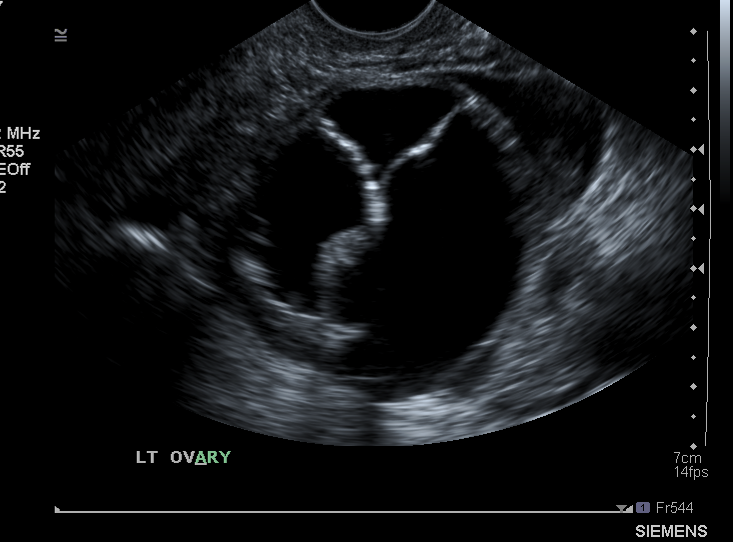

What structure is being shown here? (obtained via TVS)

Ovary

What type of mass is shown

Cyst becaue there is mainly fluid in it - i.e. black filled